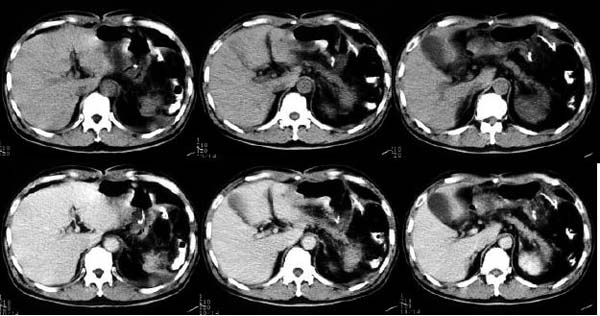

- Age/Sex: 76F

- Chief Complaint: 嫻晹堎忢堿塭

- Images: (click each image to

magnify)

- X-CT

-

- Nuclear

Tl-201 Early

Tl-201 Delayed

F-18 FDG